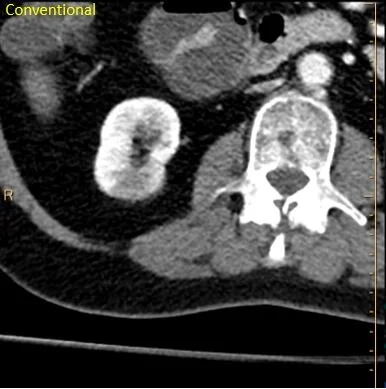

Hypodensity right kidney lower pole. Could be pyelonephritis or infarct.

Absent iodine uptake. Still could be pyelonephritis or infarct.